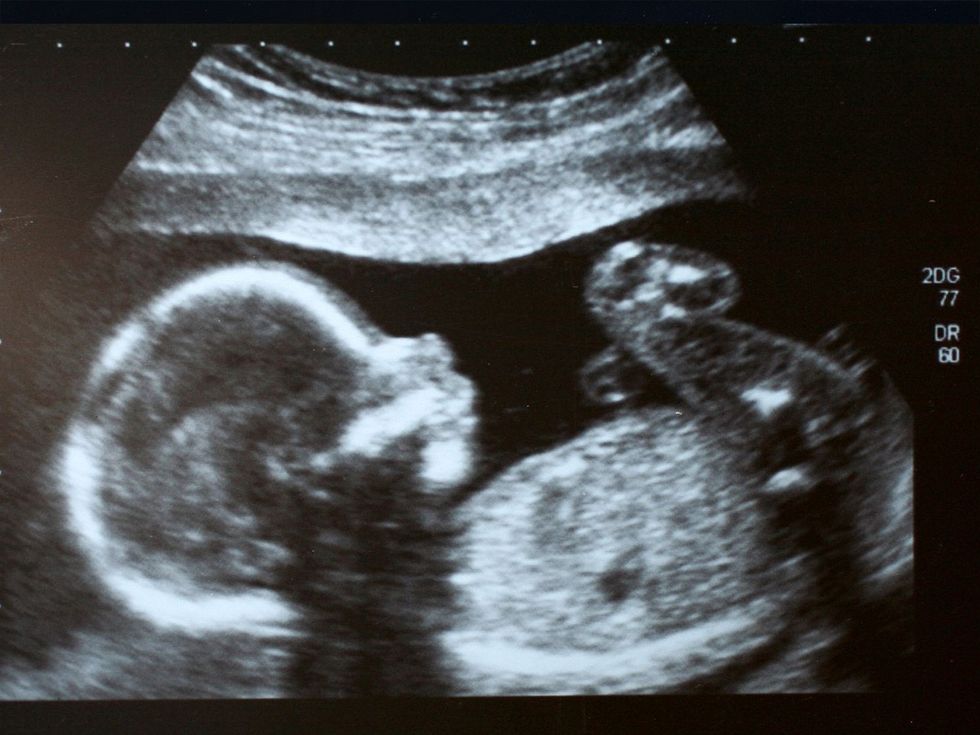

It has become increasingly common to wait until later in life to start having children. That means the oftentimes already-challenging process of conceiving often requires medical help. One of the more successful techniques is in vitro fertilization (IVF), an expensive process that often requires multiple attempts. In one attempt, researchers were able to capture, in real-time, a human embryo implanting itself on an artificial uterine wall.

This was the first time the process of embryo attachment was recorded—not only in real time but also in 3D. The researchers from the Institute of Bioengineering of Catalonia (IBEC) published their project in August 2025 in Science Advances. The manufactured platform is composed of a gel created from collagen and various proteins needed for basic embryo development. This artificial structure undergoes fluorescent imaging and microscopy. The results reveal and detail the mechanical interactions of the embryo.

Head of Bioengineering in Reproductive Health for IBEC and co-author of the study Samuel Ojosnegros said, "We have observed that human embryos burrow into the uterus, exerting considerable force during the process. These forces are necessary because the embryos must be able to invade the uterine tissue, becoming completely integrated with it." He continued, "It is a surprisingly invasive process... [that] had never been observed before."